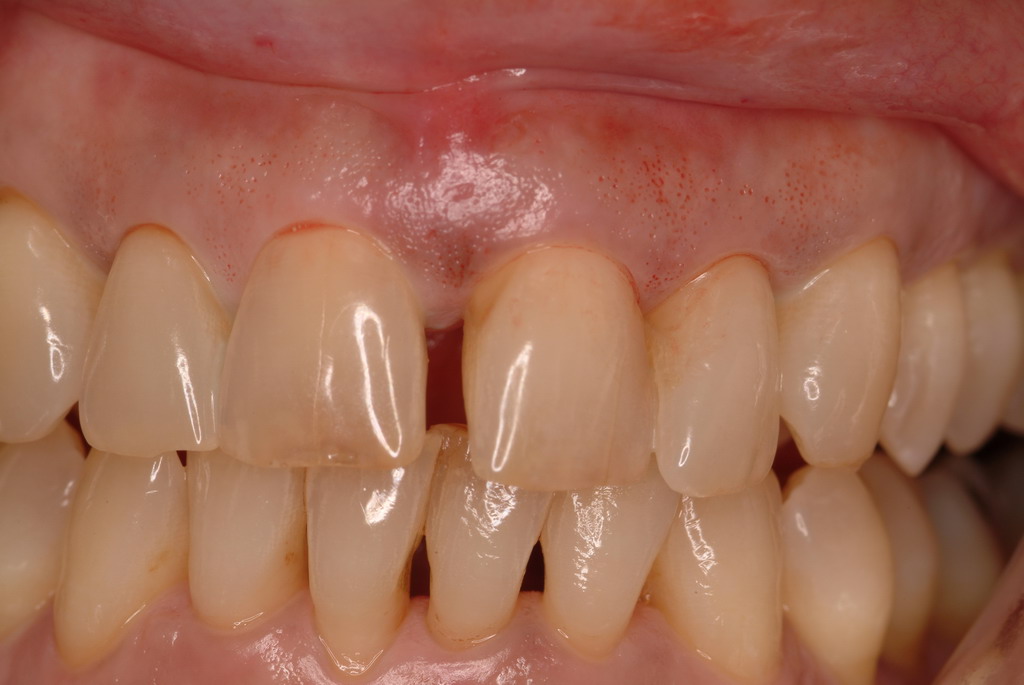

At the 13-month postoperative visit, the patient who had initially been referred for extraction and an implant still has the tooth with minimal probing depths and no mobility (Figure 20). She reported that she is happy that she did not have to have her canine extracted.

The 13-month postoperative radiograph. Significant regeneration is suggested.

Figure 20